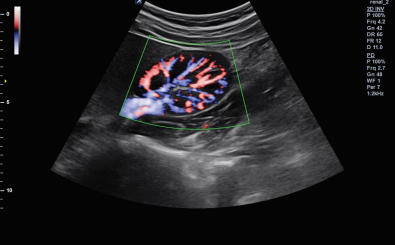

CLINICAL IMAGES

臨床影像

Abdomen

Directional Power Doppler Imaging